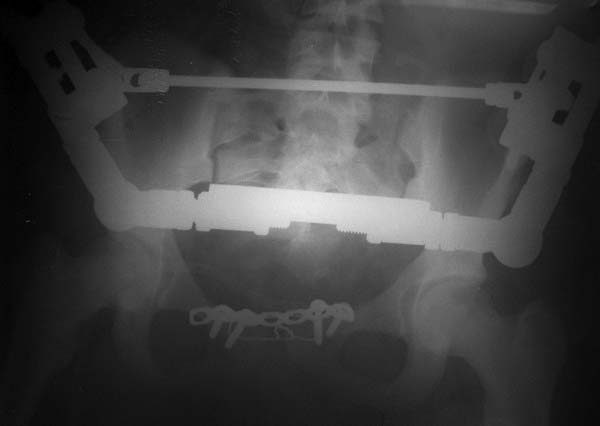

Девочка 14 лет. Кататравма (падение с высоты 4-5 этажа). Вертикально нестабильный перелом таза со смещением, разрывом лонного и левого подвздошно-крестцового сочленения, перелом крестца, открытый перелом костей голени. Ребёнок оперирован на 10-е сутки после травмы - выполнили максимально возможную репозицию на ортопедическом столе, синтез лонного сочленения реконструктивной пластиной (из имеющихся пластин - на 7 дыр - самая длинная, получилось только по 2 шурупа с каждой стороны, поэтому пришлось подстраховаться проволокой), АВФ. Задний комплекс не фиксировали ввиду отсутствия канюлированных (да и неканюлированных)шурупов должной длинны.В настоящий момент перед нами стоит вопросов:1. Обязательно ли фиксировать подвздошно-крестцовое сочленение, либо фиксации АВФ будет достаточно? Аппарат стоит достаточно стабильно, девочка при перемещениях в пределах постельного режима болевых ощущений не испытывает.2. Что делать с отломком крестца, который довольно значительно смещён кпереди? В настоящий момент никаких проблем с дефекацией у больной нет, хотя, глядя на КТ, создаётся впечатление, что отломок прямо-таки лежит на прямой кишке. Репонировать-фиксировать? Просто удалить? Вообще не трогать? Не создаст ли он в дальнейшем проблем во время родов?Хотелось бы знать мнение уважаемых коллег.Заранее спасибо.